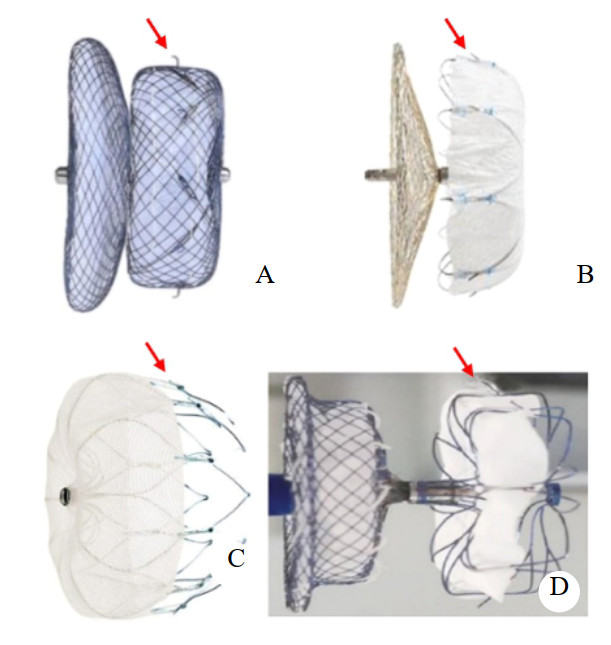

本院LAAC术后发生延迟性心包积液/ 心脏压塞行急诊心包引流患者有以下特点:①均为老年房颤患者;②左心耳位置除1例与左上肺静脉毗邻外,均与肺动脉贴合,并且1例同时与肺动脉和左上肺静脉毗邻;③左心耳为菜花及鸡翅型,此类患者左心耳较大,选用了更大尺寸封堵器,且术中调整及更换封堵器比例显著增加;④心脏压塞发生率LACbes最高,LAmbre和Watchman均在1% 以内且差异无统计学意义。有报道肺动脉与左心耳近中端毗邻比例为28%[6],本院LAAC后复查左心房CTA,左心耳封堵器锚定区毗邻肺动脉及左上肺静脉比例为20%;病例LACbes发生率最高,为Watchman和LAmbre的6倍,Laager病例数少难以比较。LAcbes为未分体型双盘左心耳封堵器,由镍钛合金丝编织而成,固定盘为柱状结构,高5 mm,固定盘外2/3处周围一圈方向分布于向内的锚钩,其固定盘压缩后反弹张力显著增加[29]。笔者认为这可能是导致延迟性心脏压塞发生率增加的最主要的原因。不同类型封堵器结构见图 3。对此笔者认为,左心耳毗邻解剖结构及封堵器设计是LAAC后发生心脏压塞的重要内因和外因,尽管其没有直接的因果关系。

| A:LAcbes;B:LAmbre;C:Watchman;D:Laager;红色箭头指向锚钩 图 3 不同类型的左心耳封堵器,锚钩至封堵伞面距离各不相同 Fig 3 Four different types of left atrial appendage occluders, the distance between anchor hook and occluder surface was different |